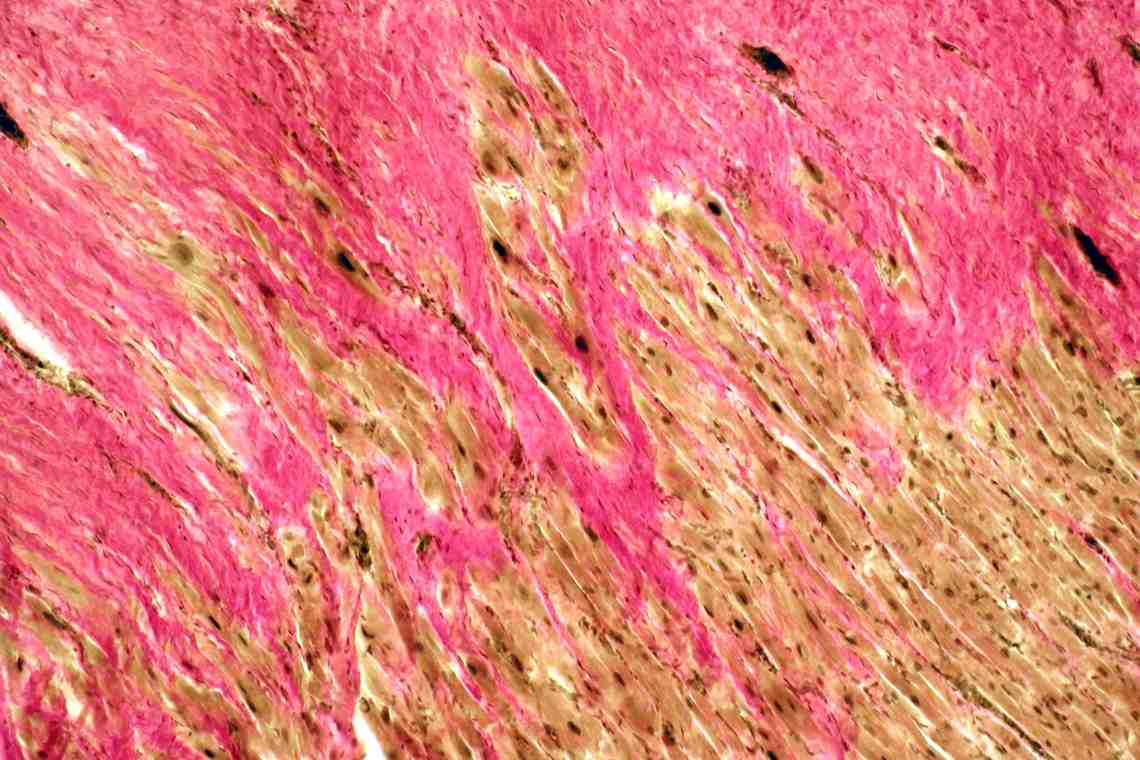

Межуточный миокардит: гистологические исследования